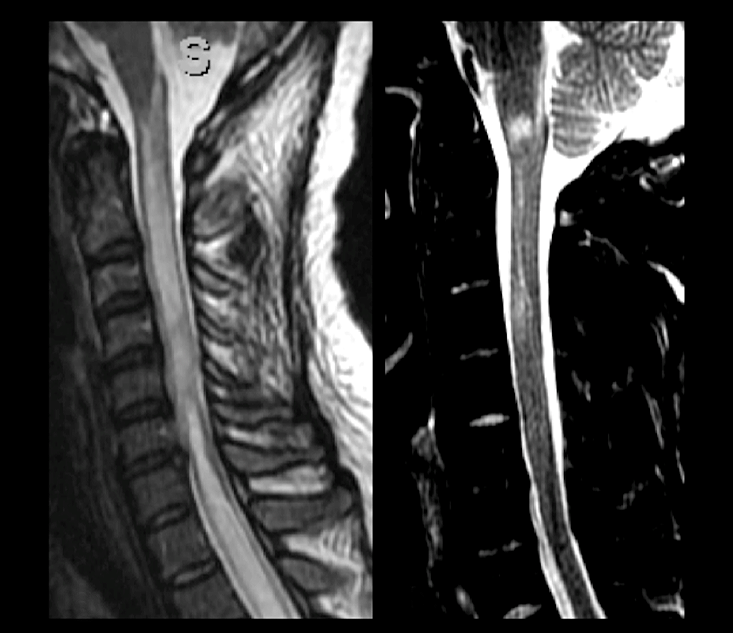

Figura 5 | Distribuição de lesões sugestivas do espectro da NMO. A imagem (A) demonstra uma mielite transversa longitudinalmente extensa (LETM) com localização centromedular, ao redor do canal central da medula. Em (B), vemos uma lesão extensa na superfície ependimária, delineando o esplênio do corpo caloso e a superfície do átrio do ventrículo lateral direito. Outras localizações frequentes de lesões de NMOSD são o quiasma óptico (C), o quarto ventrículo (D) e a superfície do terceiro ventrículo (E), com acometimento da região dos tálamos e diencéfalo. A última imagem (F) demonstra um esquema, em linhas pontilhadas, de regiões ricas em receptores de AQP4.

Nas apresentações medulares, ambos os grupos apresentam uma frequência alta de mielites transversas longitudinalmente extensas (com extensão longitudinal igual ou superior à de três corpos vertebrais). No entanto, cerca de um terço dos pacientes anti-MOG+ pode ter mielites curtas únicas ou multifocais (figura 6). Do ponto de vista de localização, os indivíduos anti-MOG+ exibem uma frequência um pouco mais elevada de lesões no cone medular no primeiro surto. Essas lesões, porém, não são patognomônicas desses pacientes. Por outro lado, indivíduos com NMOSD anti-AQP4+ aparentemente têm uma frequência maior de acometimento da área postrema. Outro achado potencialmente distintivo entre os dois quadros são as bright spotty lesions, caracterizadas por focos altamente hidratados nas lesões medulares, com sinal igual ou superior ao liquor, que parecem ser mais frequentes nos pacientes anti-AQP4+, podendo estar presentes em cerca de 30% a 50% das mielites agudas desses indivíduos.

Figura 6 | Lesões medulares em paciente com NMOSD (A) demonstram uma mielite transversa longitudinalmente extensa, com acometimento da transição bulbomedular e da área postrema. A imagem (B) mostra paciente anti-MOG+ com lesões medulares mais curtas, também acometendo a junção bulbomedular.